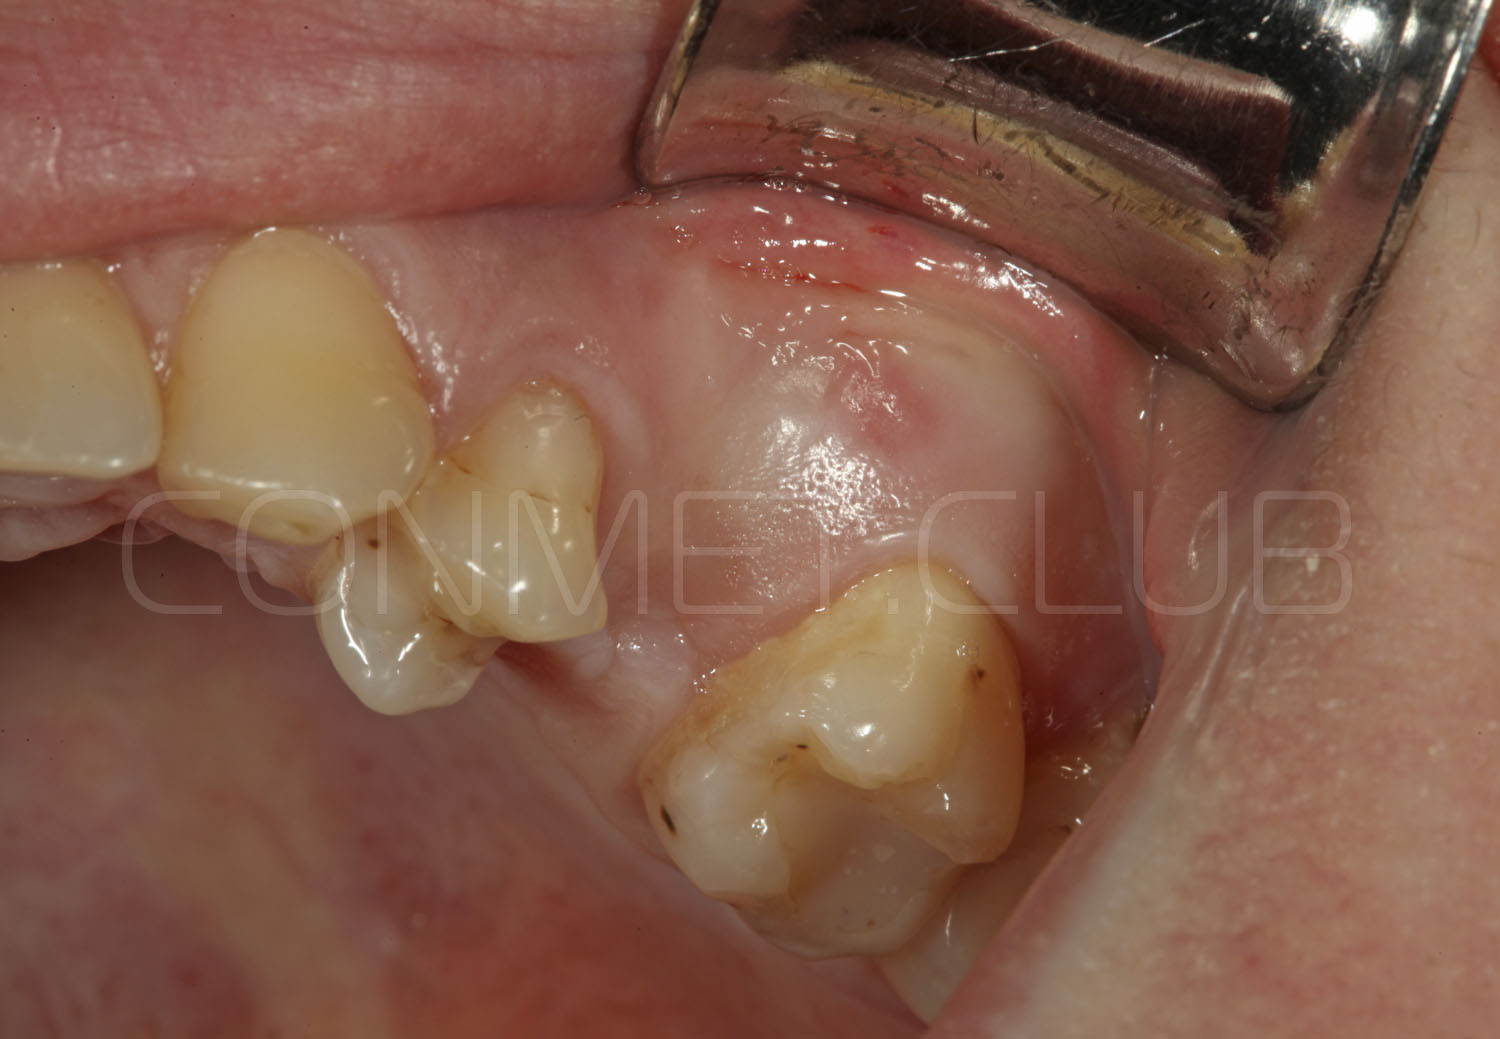

Имплантат устанавливается в подготовленное ложе. Так как не производится широкого откидывания слизисто надкостничных лоскутов и операция проводится через маленькое перфорационное отверстие, кровоточивость и сама операционная травма - минимальные.

После установки имплантата Конмет,  на период интеграции (6-8 недель), фиксируется винт заглушка. В подобных случаях швы никогда не накладываются, а пефорационное отверстие в слизистой оболочке закрывается дентальным Солкосерилом.